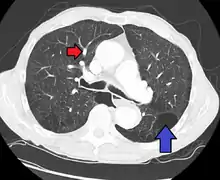

CT scan

Signs of pulmonary hypertension on CT scan of the chest are:

- Enlargement of the pulmonary trunk (measured at its bifurcation). It is, however, a poor predictor of pulmonary hypertension in patients with interstitial lung disease.[62]

- A diameter of more than 27 mm for women and 29 mm for men is suggested as a cutoff.[62]

- A cutoff of 31.6 mm may be a more statistically robust in individuals without interstitial lung disease.[62]

- Increased ratio of the diameter of the main pulmonary artery (pulmonary trunk) to the ascending aorta (measured at its bifurcation).

- Increased diameter ratio of segmental arteries to bronchi. This finding in three or four lobes, in the presence of a dilated pulmonary trunk (≥29 mm), and absence of significant structural lung disease confers a specificity of 100% for pulmonary hypertension.[62]

- Mural calcification in central pulmonary arteries is most frequently seen in patients with Eisenmenger's syndrome.[62]